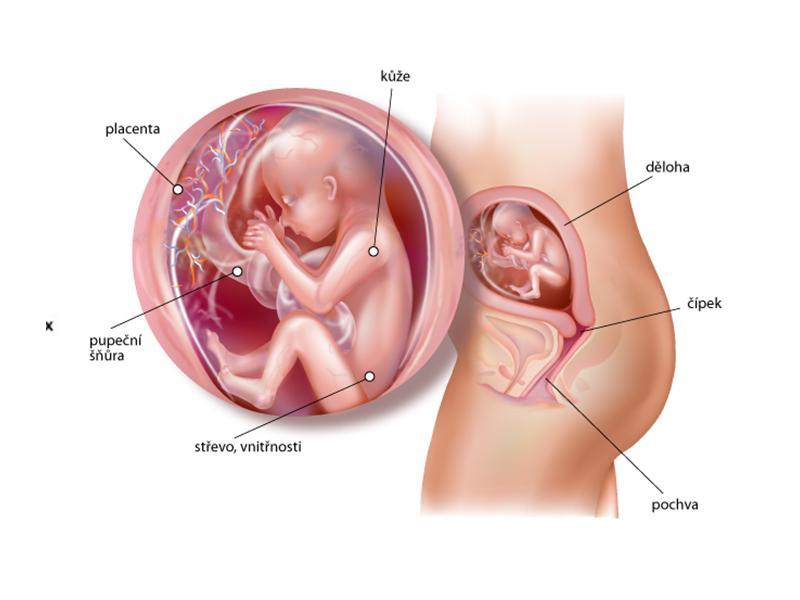

Kolem 20. týdne těhotenství byste měla absolvovat II. ultrazvukový screening (20–22. týden těhotenství). Toto vyšetření se specializuje na odhalení případných vývojových vad plodu, dále se zjišťuje uložení placenty, množství plodové vody a růst plodu. V případě nejasného nálezu nebo zvýšeného rizika se doplňuje podrobné vyšetření srdce plodu lékařem – specialistou.

Opět se přichystejte na vyšetření v prenatální poradně. Podstoupíte ultrazvukový screening plodu (lze v intervalu 18. až 20. týden). Jeho cílem je zhodnotit růst plodu a stav jednotlivých orgánových skupin. Pokud by plod měl nějakou strukturální odchylku (srdeční vada, obličejový rozštěp), lze ji odhalit.

Volný pohyb plodu ve všech směrech zajišťuje pupečník, jehož délka dosahuje asi 50 cm. Cévy, které zásobují plod kyslíkem, živinami a dalšími důležitými látkami, probíhají v pupečníku spirálovitě. To je chrání před poškozením při natažení pupečníku.

V amniovém vaku je asi 350 ml plodové vody. Vzhledem k tomu, že plod roste v této době rychleji, než se zvětšuje děloha, začíná docházet k jeho občasným kontaktům s děložní stěnou – těhotná žena vnímá pohyby miminka.

Dítě je uprostřed svého prenatálního vývoje. Kůže je složená ze čtyř vrstev, je již pevnější, než tomu bylo například před dvěma týdny. Dozrávají spoje a nervové buňky v centrální nervové soustavě, které odpovídají na podněty smyslových orgánů. Holčičkám se právě v tuto dobu formuje pochva, v jejích vaječnících je nyní založeno na 2 miliony vajíček, kterých však v době narození zůstane polovina. Vývoj smyslů je nyní ve svém klíčovém stadiu. Dítě je stále drobné, ale rychle roste. Užívá si protahování končetin.

Od 20. týdne těhotenství se pro určení délky plodu používá součet délky hlavičky, trupu a nohou. Ve 20. týdnu těhotenství měří plod zhruba 25,5 cm. Váha plodu je nyní zhruba 300 g.